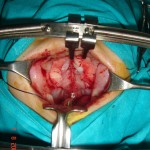

The commonly misleading history given by the parents is that the child may have had a trivial trauma or an insect bite. However, for the clinician the golden rule should be ‘Any acute scrotum is testicular torsion unless proved otherwise’. Investigations like ultrasound and color doppler may be done to help in the diagnosis. However, in the event of any doubt, it is safest to do a surgical exploration of the scrotum. The other uncommon causes of acute scrotum are acute epidydymo orchitis, scrotal abscess, idiopathic scrotal oedema and torsion of appendix of the testis. ●

Acute Scrotum (Right scrotal Abscess)

Torsion of Left Undescended Testis (Pre operative and Operative Photo)

Acute Scrotum

Torsion Testis (Pre and Per operative photo)